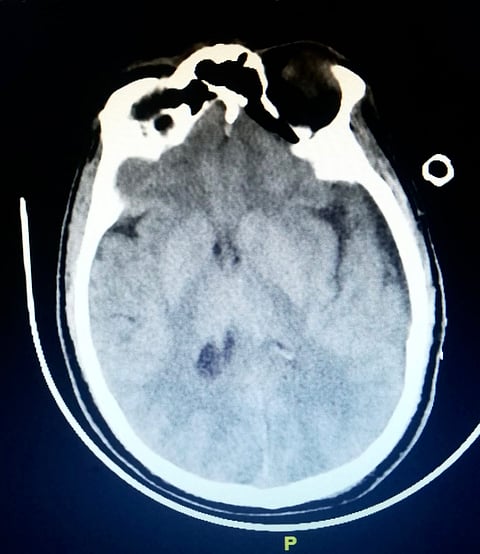

وأوضحت صحة الطائف في بيان وصل "سبق" أنهُ "بعد إجراء الأشعة المقطعية للمخ تبين وجود تجمع دموي ما بعد الحاد كبير تحت الأم الجافية على الفص الأمامي والجانبي والصدغي الأيسر بالمخ، مع بداية تحرك لهم إلى الجانب الأيمن "بداية فتق مميت للمخ"، كما أظهرت التحاليل نقصًا شديدًا في الصفائح الدموية".